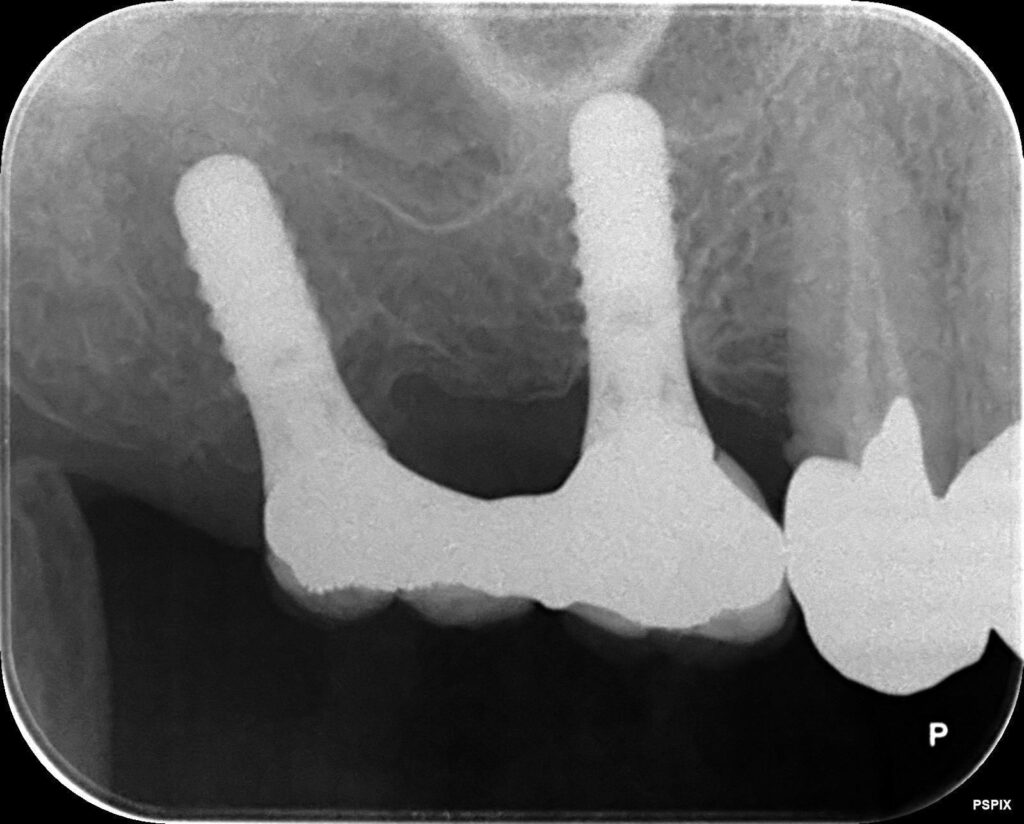

治療内容 右上6番7番の欠損

治療期間 2005年2月22日~2005年7月7日

費用 800,000円

20年前、重度の歯周病で歯を失い、インプラント治療を行った患者さんのケースです。治療後は定期メンテナンスを欠かさず、ご自身でも丁寧なセルフケアを続けてこられました。

その結果、骨の吸収も minimal で、インプラント体(フィクスチャー)は20年経っても非常に安定しています。

・レントゲンでの骨吸収の比較

とくにレントゲン比較は非常に重要で、初期と現在を見比べることで微細な変化を早期に発見できます。